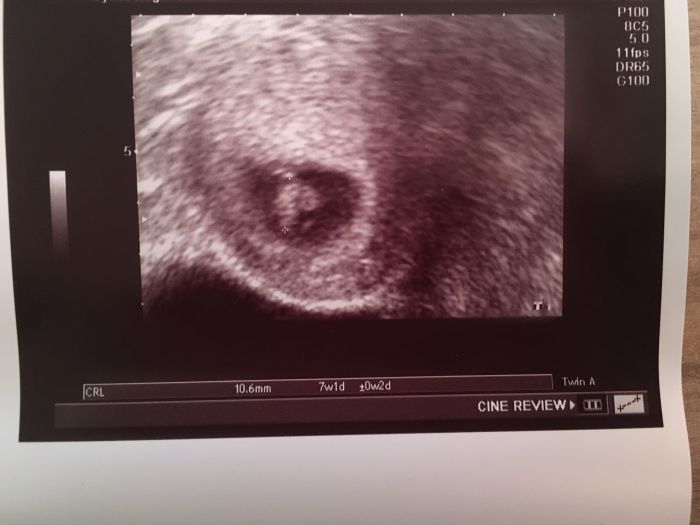

Ahoj holky, dneska jsem byla tedy na kontrole a termín mam 6.6. 2020. Všechno je zatím v pořádku tak jsem ráda. Podle utz to vypadá na 7+2 momentálně. Akorát jsem myslela, že tam dneska ani nedojedu, během dopoledne jsem třikrát zvracela a celkově mi je pořad tak nějak špatně. Tak snad to poleví, všem držím palečky na kontrolách :)

Autor: FRox 21.10.2019 v 15:08

Dokonce jsem i viděla srdíčko, takže paráda. :) všechno je zatím tak jak má.

Bejly a FRox gratuluji ke krásným snímkům a potvrzení od dr